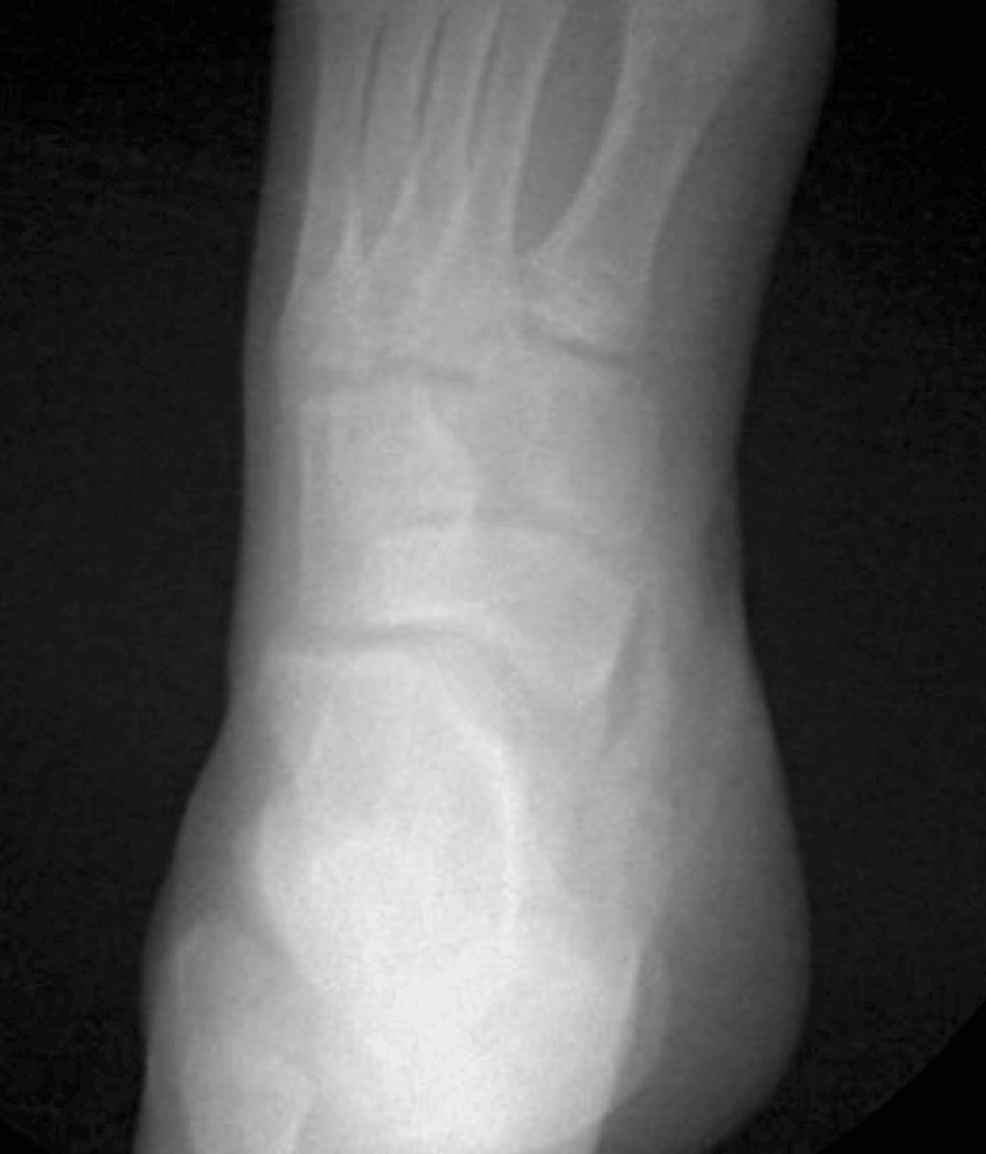

Accessory navicular bone on plain Xray in 5 cases; case 1 (type II);... Download Scientific Accessory Navicular Bone Percentage The accessory navicular bone is described to be an anatomical variant present in 4 to 21% of the human population and can be. An accessory navicular is an extra bone that is on the inner center arch of the foot. Acessory navicular is a common idiopathic condition of the foot that presents with an enlargement of the navicular bone. How. Accessory Navicular Bone Percentage.

The foot radiographs of three different types of accessory navicular bone. Download Scientific Accessory Navicular Bone Percentage The accessory navicular bone is described to be an anatomical variant present in 4 to 21% of the human population and can be. Up to 2.5 percent of individuals are born with the accessory navicular. Does accessory navicular syndrome get worse. Acessory navicular is a common idiopathic condition of the foot that presents with an enlargement of the navicular bone.. Accessory Navicular Bone Percentage.